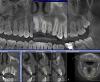

xo4ysoxranitzyb Опубликовано 17 августа, 2009 Поделиться Опубликовано 17 августа, 2009 Зравствуйте. Мне 22 года, девушка, г.Санкт-Петербург, гр.крови "1+".Мне лет 8 назад ставили пломбу(без удаления нерва) на 22 зуб(верхняя левая двоечка). 7 месяцев назад он стал побаливать - обратилась к стоматологу. Оказалось, что нерв умер сам по себе(не болезненно), а на зубе образовалась киста. Почистили каналы, поставили лекарство и временную пломбу - попробовали терапевтическое лечение. Но через две недели появилась припухлость десны в области корня 2-ки. Открыли зуб, разрезали десну с наружной стороны. В тот же день появилась припухлость десны с внутренней стороны. Антибиотики внутренне, антисептик(полоскание) - припухлость прошла. Болезненных ощущений не было. Зуб оставался открыт 6 месяцев(моя вина, надеялась - что пополощу травками - пройдет), во время еды вставляла ватку.Сейчас зуб начал побаливать. Обратилась к стоматологу. Начала терапевтическое лечение, пока - меняют лекарство через пару-тройку дней, пропила Ровамицин 7 дней. Не болит, не воспаляется. ------------Врач-терапевт говорит, что есть шанс вылечить терапевтически.Врач-хирург говорит, что киста очень большая, объемная и сложной формы. Что она очень близко расположена к носовой перегородке и к соседнему зубу. Что резекцию делать бесполезно, т.к. киста очень высоко поднялась по корню зуба. Что необходимо удалять зуб, причем срочно - т.к. она растет и скоро повредит носовую перегородку, а потом и соседний зуб(если еще не добралась до него).=====Подскажите, пожалуйста 1. Каков шанс вылечить терапевтически2. Возможна ли резекция верхушки корня, с сохранением зуба(!)3. Если нет возможности оставить зуб - то что будет вместо него(если вырезать кисту - то там практически нет надкостницы - не на что ставить имплант наверное). Но пилить соседние зубы - передние - это совсем плохо, я молодая еще.4. Куда лучше обратиться(поликлиника)ПОМОГИТЕ!!! Мне очень важно сохранить этот зуб! У меня на руках томограмма зубной полости, может какие другие снимки(ракурсы) прикрепить? Ссылка на комментарий